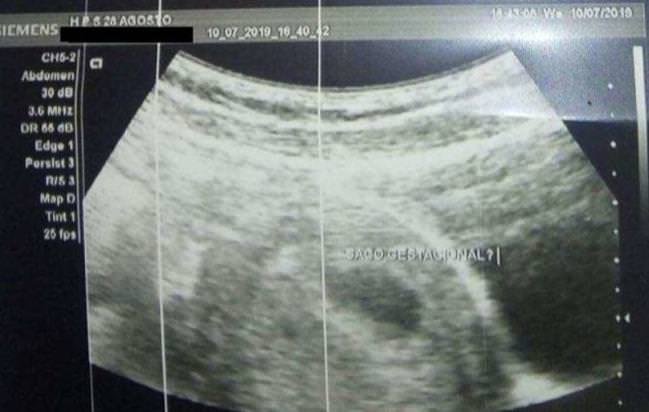

A Venezuelana de 29 anos, identificada pelas iniciais A.H.Y que denunciou o Padre da Arquidiocese de Manaus de 60 anos de nome não divulgado, está grávida de um mês e duas semanas, o resultado do exame foi informado pelo pai da imigrante nesta quinta-feira (11). O teste de gravidez foi realizado no Hospital e Pronto-Socorro 28 de Agosto no início desta semana, depois que a mulher desconfiou que estava grávida.

De acordo com o pai, o exame de gravidez foi feito no Hospital 28 de Agosto.